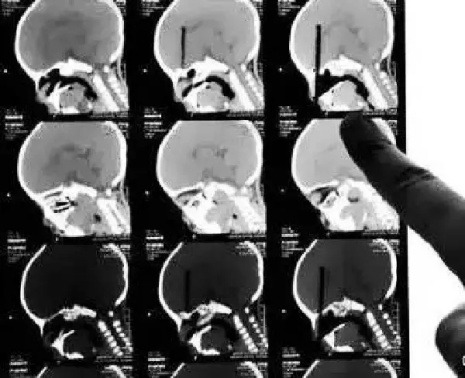

CT

CT的檢查原理是X光會斷層穿過人體,通過電腦計算后處理為二次成像。

優(yōu)點:可以斷層看,經(jīng)后處理可以顯示更多信息。

缺點:費用比X光攝影貴,且CT檢查的輻射劑量通常高于單次X光攝影。

(筷子插入小朋友眼球的CT三維重建片)